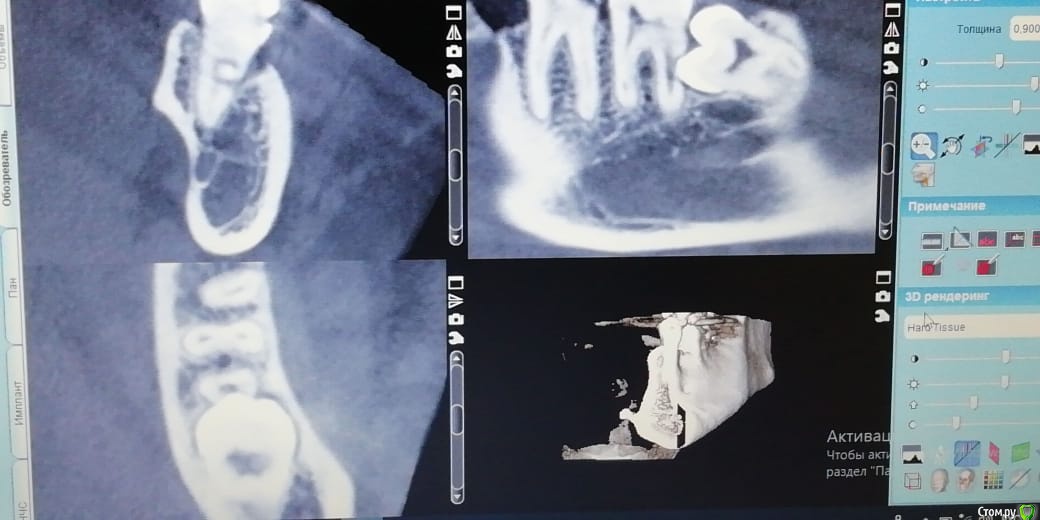

___49___ Опубликовано 30 января, 2019 Поделиться Опубликовано 30 января, 2019 (изменено) Дано на Rg: Вижу два варианта решения задачи. - могу убрать 8ку с одномоментной гемисекцией ( заранее пролеченного 7го зуба) дистального корня 7ки . Далее вкв в мезиальный корень 7ки , лечение 6ки под коронку и изготовление мостовидного протеза с опрой на 6\7 и консолью 5ка . - можно депульпировать 7ку , во время удаления 8 ки закрыть перфу прорутом . 2 вариант на мой взгляд менее прогнозируемый .... у кого какие мысли коллеги ? Изменено 30 января, 2019 пользователем ___49___ Ссылка на комментарий

___49___ Опубликовано 31 января, 2019 Автор Поделиться Опубликовано 31 января, 2019 (изменено) Процесс ведь там не кариозный,а вполне себе асептический,почему бы не убрать 8ку,заполнить лунку графтом,ушить герметично и понаблюдать?На счет асептического сомнения есть , попробую нарисовать .А 7 живой? Как пульпа реагирует?Если живой - убрать 8, дать зажить ране 3-4 недели, переоценить 7. Он вполне может остаться живым.7ка живая - на холодное реакция выраженная, но не продолжительная , перкуссия болезнена ( но это не из-за Pt а из-за соприкосновения с 8 кой) Ваше предложение интересное, как и выше предложенные варианты , спасибо всем за участие . Буду говорить с пациентом , о этапах и рисках всех вариантов . Изменено 31 января, 2019 пользователем ___49___ Ссылка на комментарий